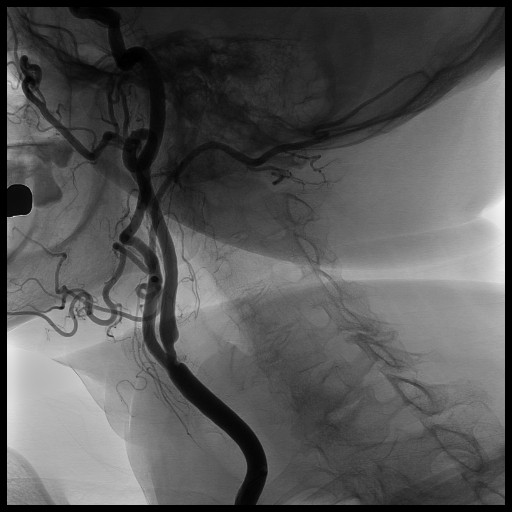

Angioplastica carotidea

Si tratta del trattamento transcatetere della aterosclerosi delle arterie carotidi e riduce il rischio di ictus cerebri. Si avvale di strumenti e dispositivi appositi ed e' una metodica largamente utilizzata con ottimi risultati.